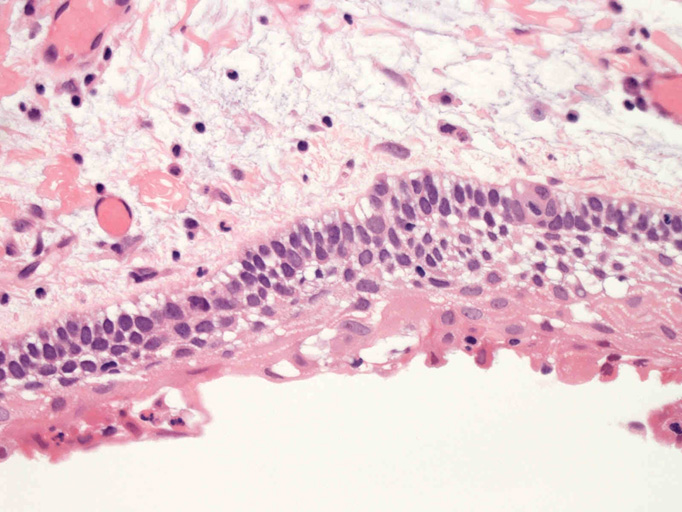

嚢胞性病変の壁を裏装する上皮はspongiosisあるいはintraepithelial edemaと棘細胞への分化を示す。7-15層の上皮で, 基底細胞はpalisadingを呈している。上皮脚は平坦で角化は認められない(Fig.01-Fig.04)。嚢胞壁はわずかにmyxoidな成分を伴うdensな膠原線維性間質からなり, その中に小さな胞巣状の歯原性上皮巣が散在している。核分裂像は認められない(Fig.05, 06)。

Fig.01Fig.02Fig.03Fig.04